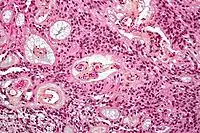

Micrograph of a myxopapillary ependymoma. HPS stain.

Micrograph of a myxopapillary ependymoma. HPS stain. Ependymoma of 4.ventricle in MRI.

About 10% of ependymomas are benign myxopapillary ependymoma (MPE).[7] MPE is a localized and slow-growing low-grade tumor, which originates almost exclusively from the lumbosacral nervous tissue of young patients.[7] On the other hand, it is the most common tumor of the lumbosacral canal comprising about 90% of all tumoral lesions in this region.[8]